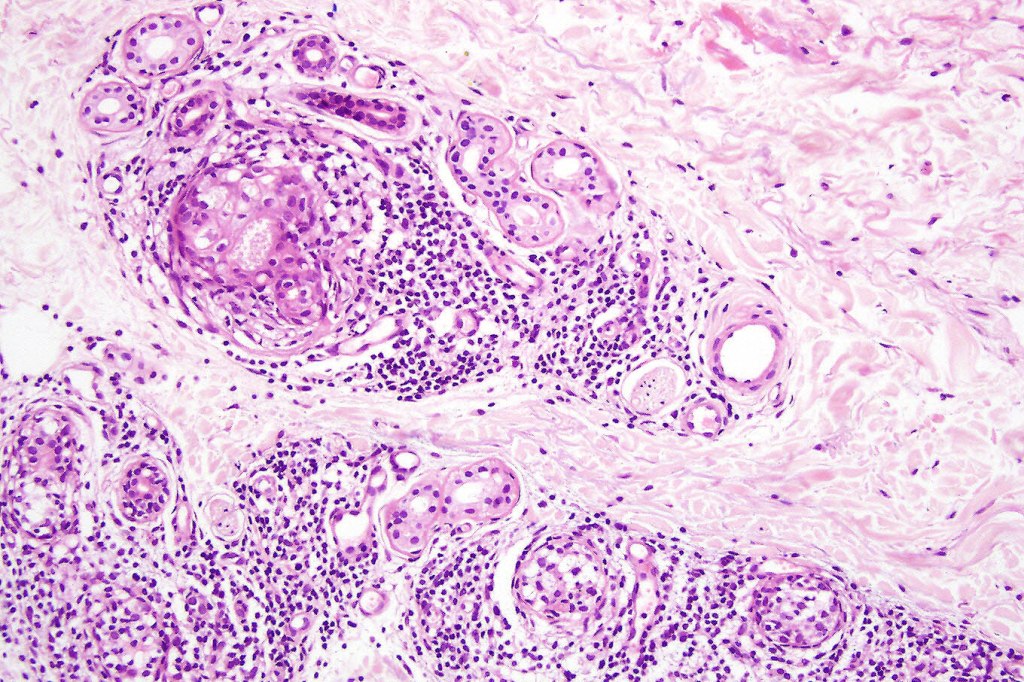

Histology may show epidermal involvement and folliculotropism. The characteristic feature is the presence of a heavy deep dermal atypical lymphocytic infiltrate surrouding and infiltrating the sweat gland & ductal epithelium. Variable numbers of Sézary cells may be present.